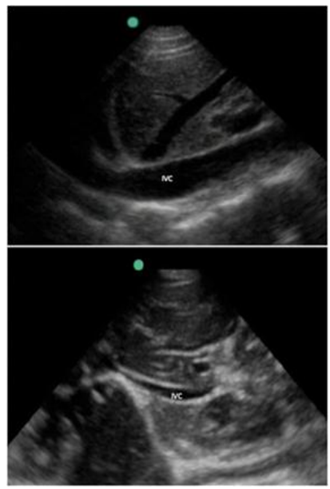

Lactente, 4 meses de vida, 6 kg, é admitido com suspeita de sepse grave. Está hipotenso com PA de 55x35 mmHg, FC de 180 bpm, extremidades frias e tempo de enchimento capilar prolongado. Foi realizado ultrassom dirigido (POCUS) de leito apresentado na imagem a seguir, demonstrando a veia cava inferior na expiração e na inspiração, além do ventrículo esquerdo hiperdinâmico com cavidades pequenas e ausência de derrame pericárdico ou outras anormalidades estruturais significativas.

Enunciado 4536521-1

Com base nos achados do ultrassom e na avaliação clínica, qual é a interpretação fisiopatológica mais provável e qual conduta deve ser realizada inicialmente?